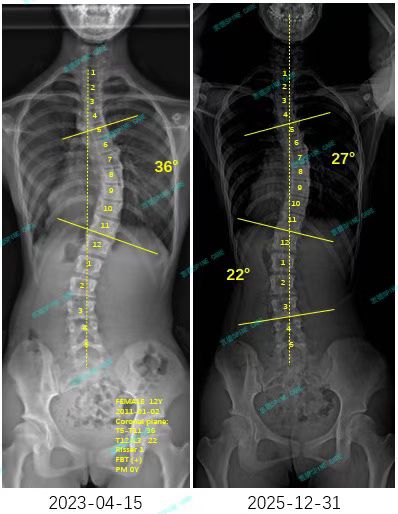

衷德脊柱,我们只关注侧弯保守治疗~

Zhongde Spine, bending no breaking ~